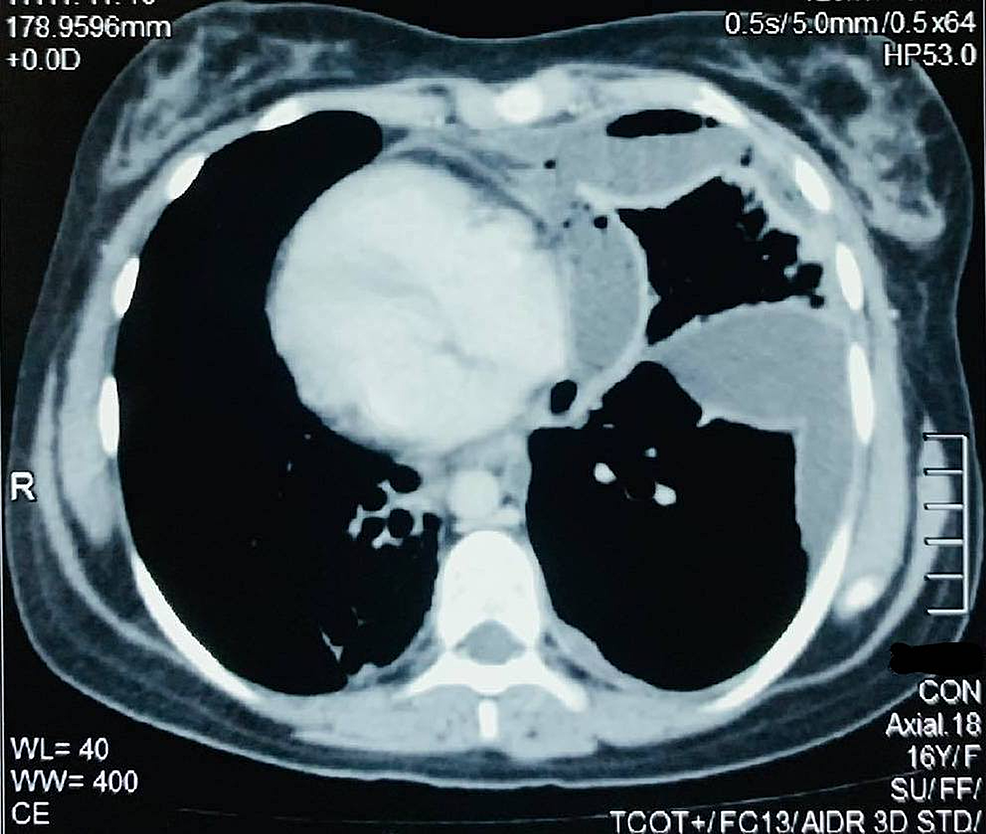

VATS decortication in pleural empyema stage II. a) Preoperative CT of Vats Decortication decortication is a surgical procedure that removes a restrictive layer of fibrous tissue overlying the lung, chest. Vats Decortication.